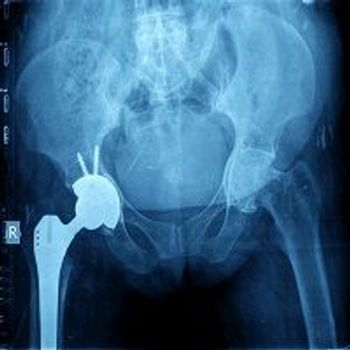

A study of patients undergoing total hip arthroplasty found that patients with psoriatic arthritis face no greater risk of poor outcomes than patients who get hip replacements because of osteoarthritis.

Study shows that patients with psoriatic arthritis and cutaneous psoriasis could be good candidates for total hip replacement.